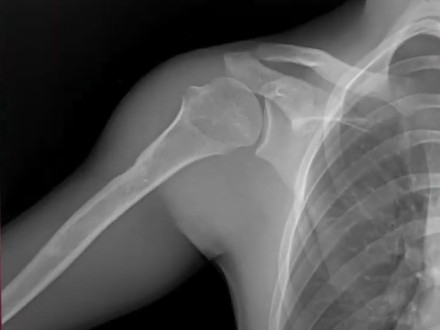

In this video from the American Academy of Orthopaedic Surgeons Annual Meeting, Michael Brandon Gottschalk, MD, FAAOS, discussed the use of dynamic digital radiography to assess upper extremity injuries.

“For us, this is a novel use. Now when you look at patients, you can do this preoperatively as well as within the clinic, and you can see their motion and you diagnose them quickly,” Gottschalk said. “Prior to [dynamic digital radiography], there was no reference standard for how you diagnosed adhesive capsulitis. Our hope is [that] with the use of this technology, we are going to develop a standard of how to diagnose some of the pathologies that are a little bit harder,” he added.